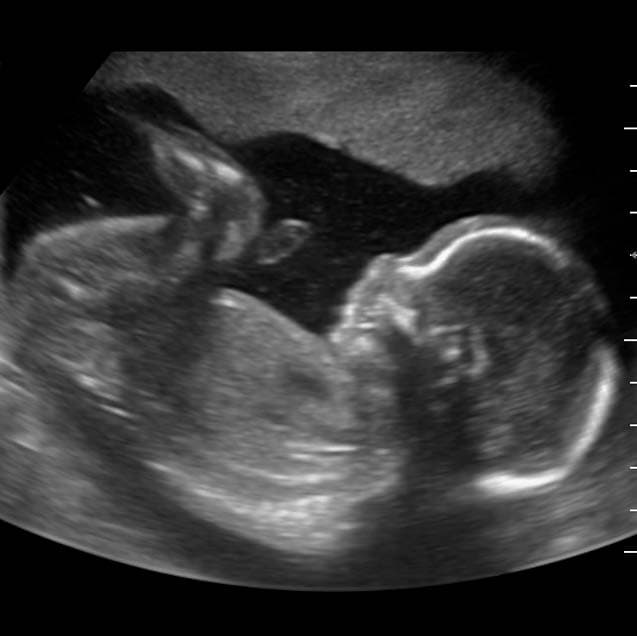

El ultrasonido estructural se realiza durante el 2do trimestre del embarazo, especialmente entre las 20-24 semanas. En esta exploración el doctor evaluará la anatomía fetal de la cabeza a los pies, observando cada una de las estructuras cerebrales, pulmones, corazón, vísceras abdominales, genitales externos, entre muchas otras cosas más.

Ultrasonido 2D

En este rubro encajan prácticamente todos los estudios de ultrasonido diagnóstico. En esta modalidad observamos la imagen clásica en blanco y negro.

- Ultrasonido Gineco-Obstétrico